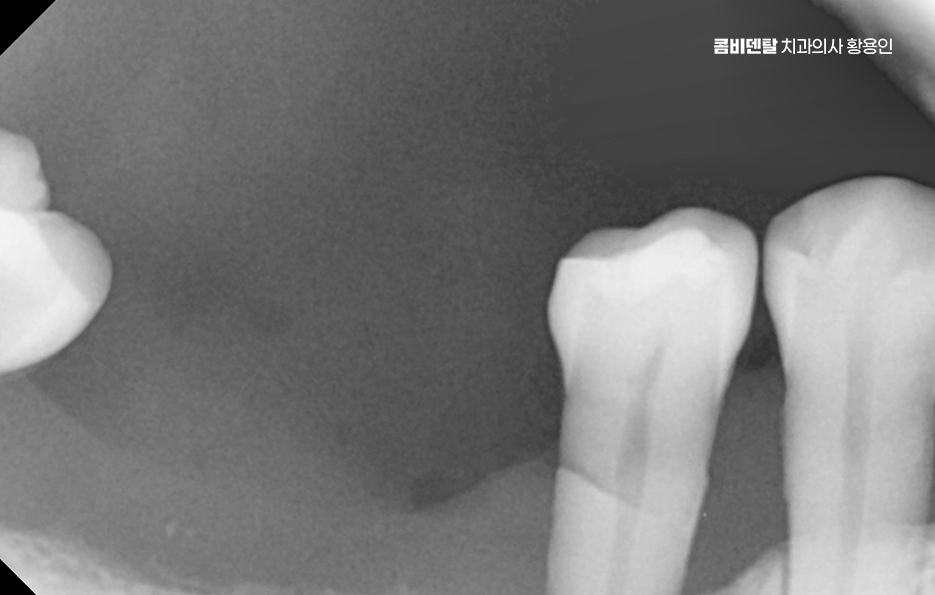

어금니 발치후 임플란트 안하면 먼저 생기는 문제는 치아 이동 현상으로 사람의 치아는 서로 의지하면서 균형을 맞추고 있는데, 어금니 하나가 빠지게 되면 그 자리를 메꾸기 위해 옆 치아들이 점점 쓰러지듯이 기울어지며 또 위아래 맞물리던 치아는 상대 치아가 사라지면 아래로 내려오거나 위로 솟구치면서 위치가 틀어질 수 있어요

결국 전체 치열이 뒤틀리고 교합이 망가지게 되는 것인데 이건 단순한 배열 문제가 아니라, 턱관절까지 영향을 줄 수 있는 변화로 이어지는 거예요.

그리고 사실 골 흡수의 문제가 무척이나 큰데 즉 잇몸뼈가 점점 사라지는 현상으로 치아가 뿌리로 잇몸뼈에 자극을 주고 있어야 뼈가 유지되는데, 치아가 빠진 상태로 계속 방치되면 그 부위 뼈는 서서히 꺼지듯이 흡수되기 시작하는 거예요.

이게 심해지면 나중에 임플란트를 하고 싶어도 뼈가 부족해서 뼈이식까지 같이 해야 하고, 수술 범위도 커지는 것이며 임플란트를 하지 않고 방치한 시간이 길수록 치료가 까다로워지고, 비용도 더 많이 들어가는 문제가 발생될 수 있었어요

그렇다면 어금니 발치 후, 임플란트를 잘 받기 위한 방법은 뭐냐 하면 첫 번째는 시기를 놓치지 않는 것인데 발치 후 3개월 내에는 임플란트를 심는 게 이상적이며 사실 요즘은 경우에 따라 ‘즉시 식립’이라고 해서 발치 당일에 임플란트를 심는 경우도 많아지고 있기 때문에 발치와 함께 임플란트 치료 계획을 세우는 것이 이상적이라 할 수 있어요